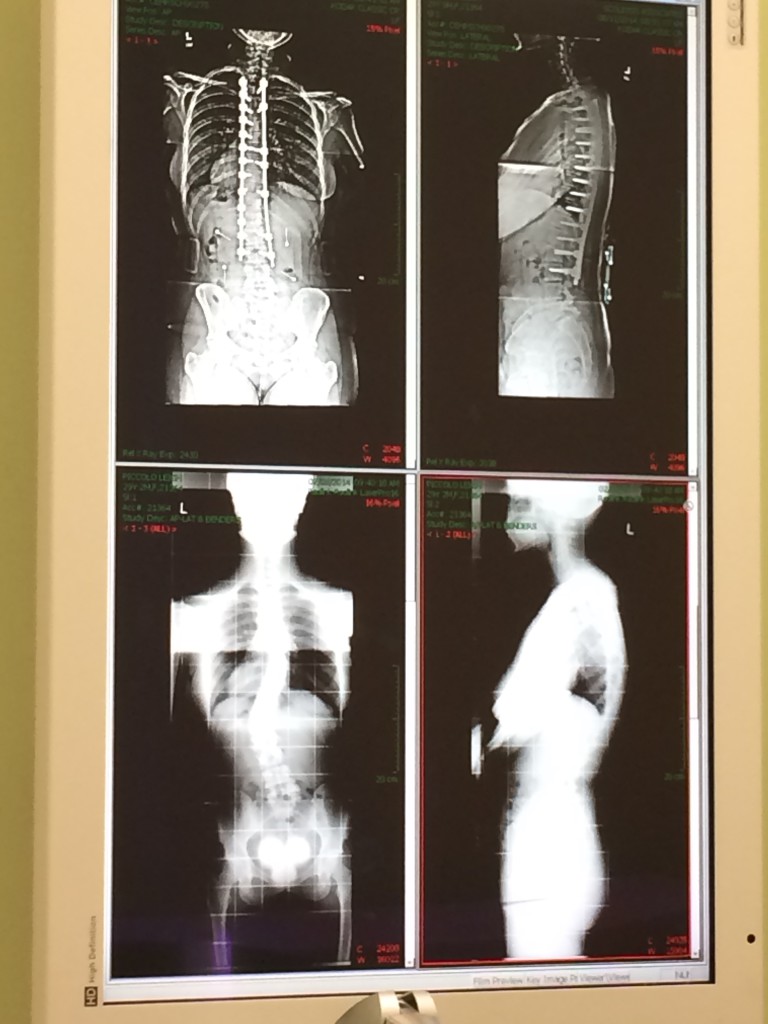

My name is Leigh and I want to share my journey through my spinal fusion surgery. I have had scoliosis since I was 13, and at the age of 30 I noticed it had been progressing more than I would like. With two curvatures in the 40 degree range I opted for a spinal fusion to correct my scoliosis which would fuse T3-L3 of my spine. While I did not get the surgery at HSS, it was very successful. I am nearly fully corrected for both my scoliosis and kyphosis. See pre and post op x-rays.